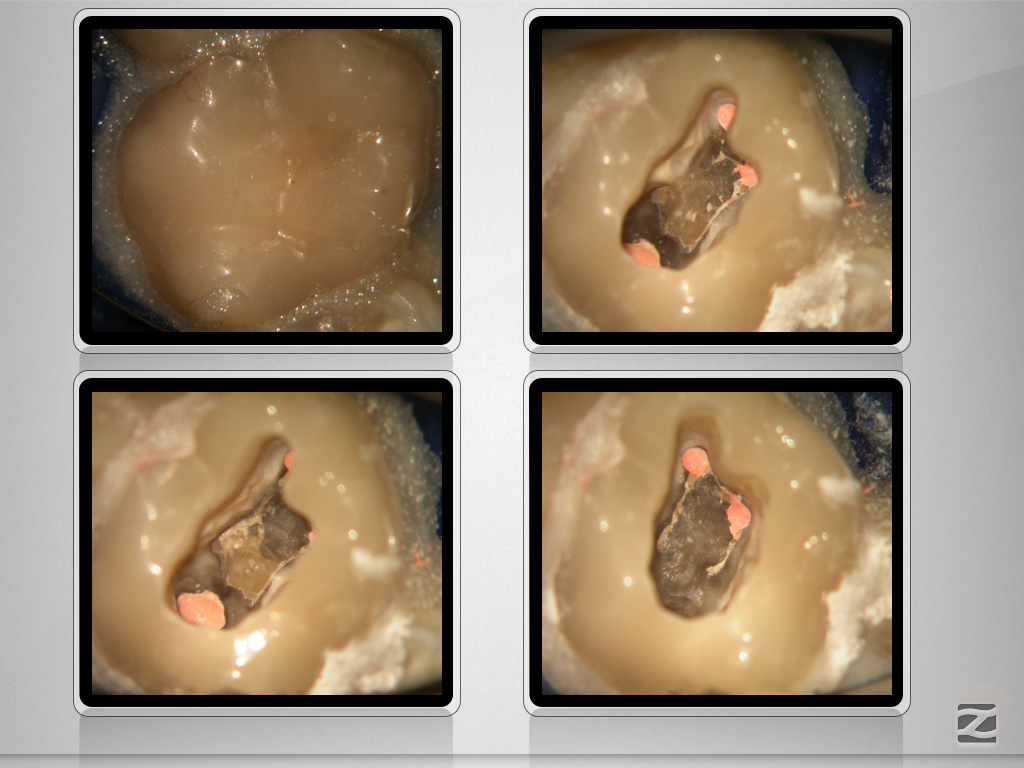

16d-007

Revision nach Resektion